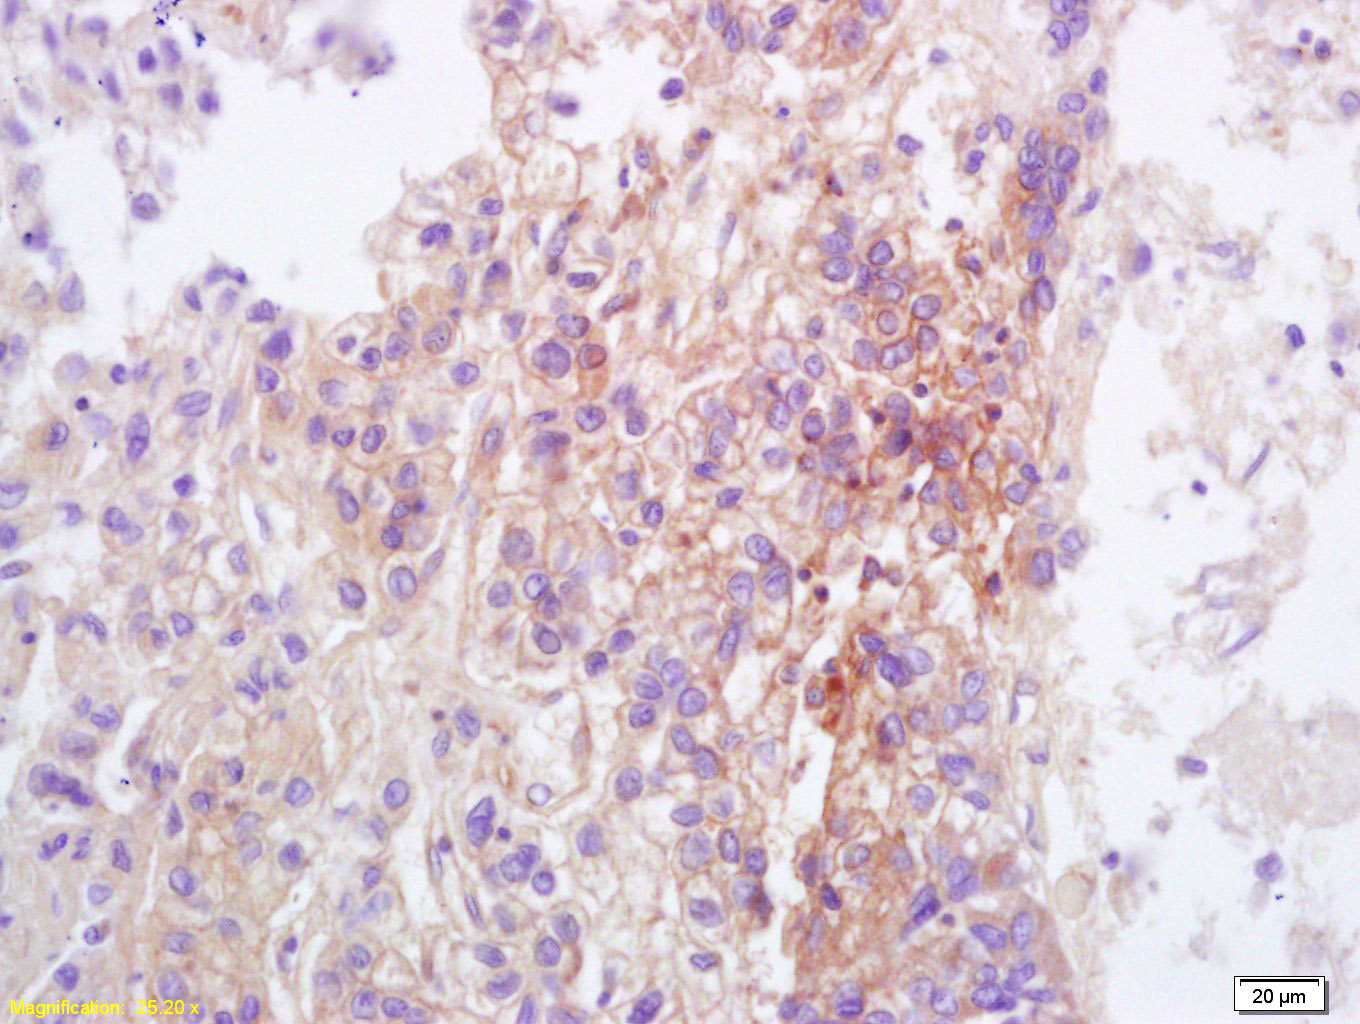

Tissue/cell: human lung carcinoma; 4% Paraformaldehyde-fixed and paraffin-embedded; Antigen retrieval: citrate buffer ( 0.01M, pH 6.0 ), Boiling bathing for 15min; Block endogenous peroxidase by 3% Hydrogen peroxide for 30min; Blocking buffer (normal goat serum,C-0005) at 37℃ for 20 min; Incubation: Anti-TRPC3 Polyclonal Antibody, Unconjugated(bs-6702R) 1:200, overnight at 4°C, followed by conjugation to the secondary antibody(SP-0023) and DAB(C-0010) staining